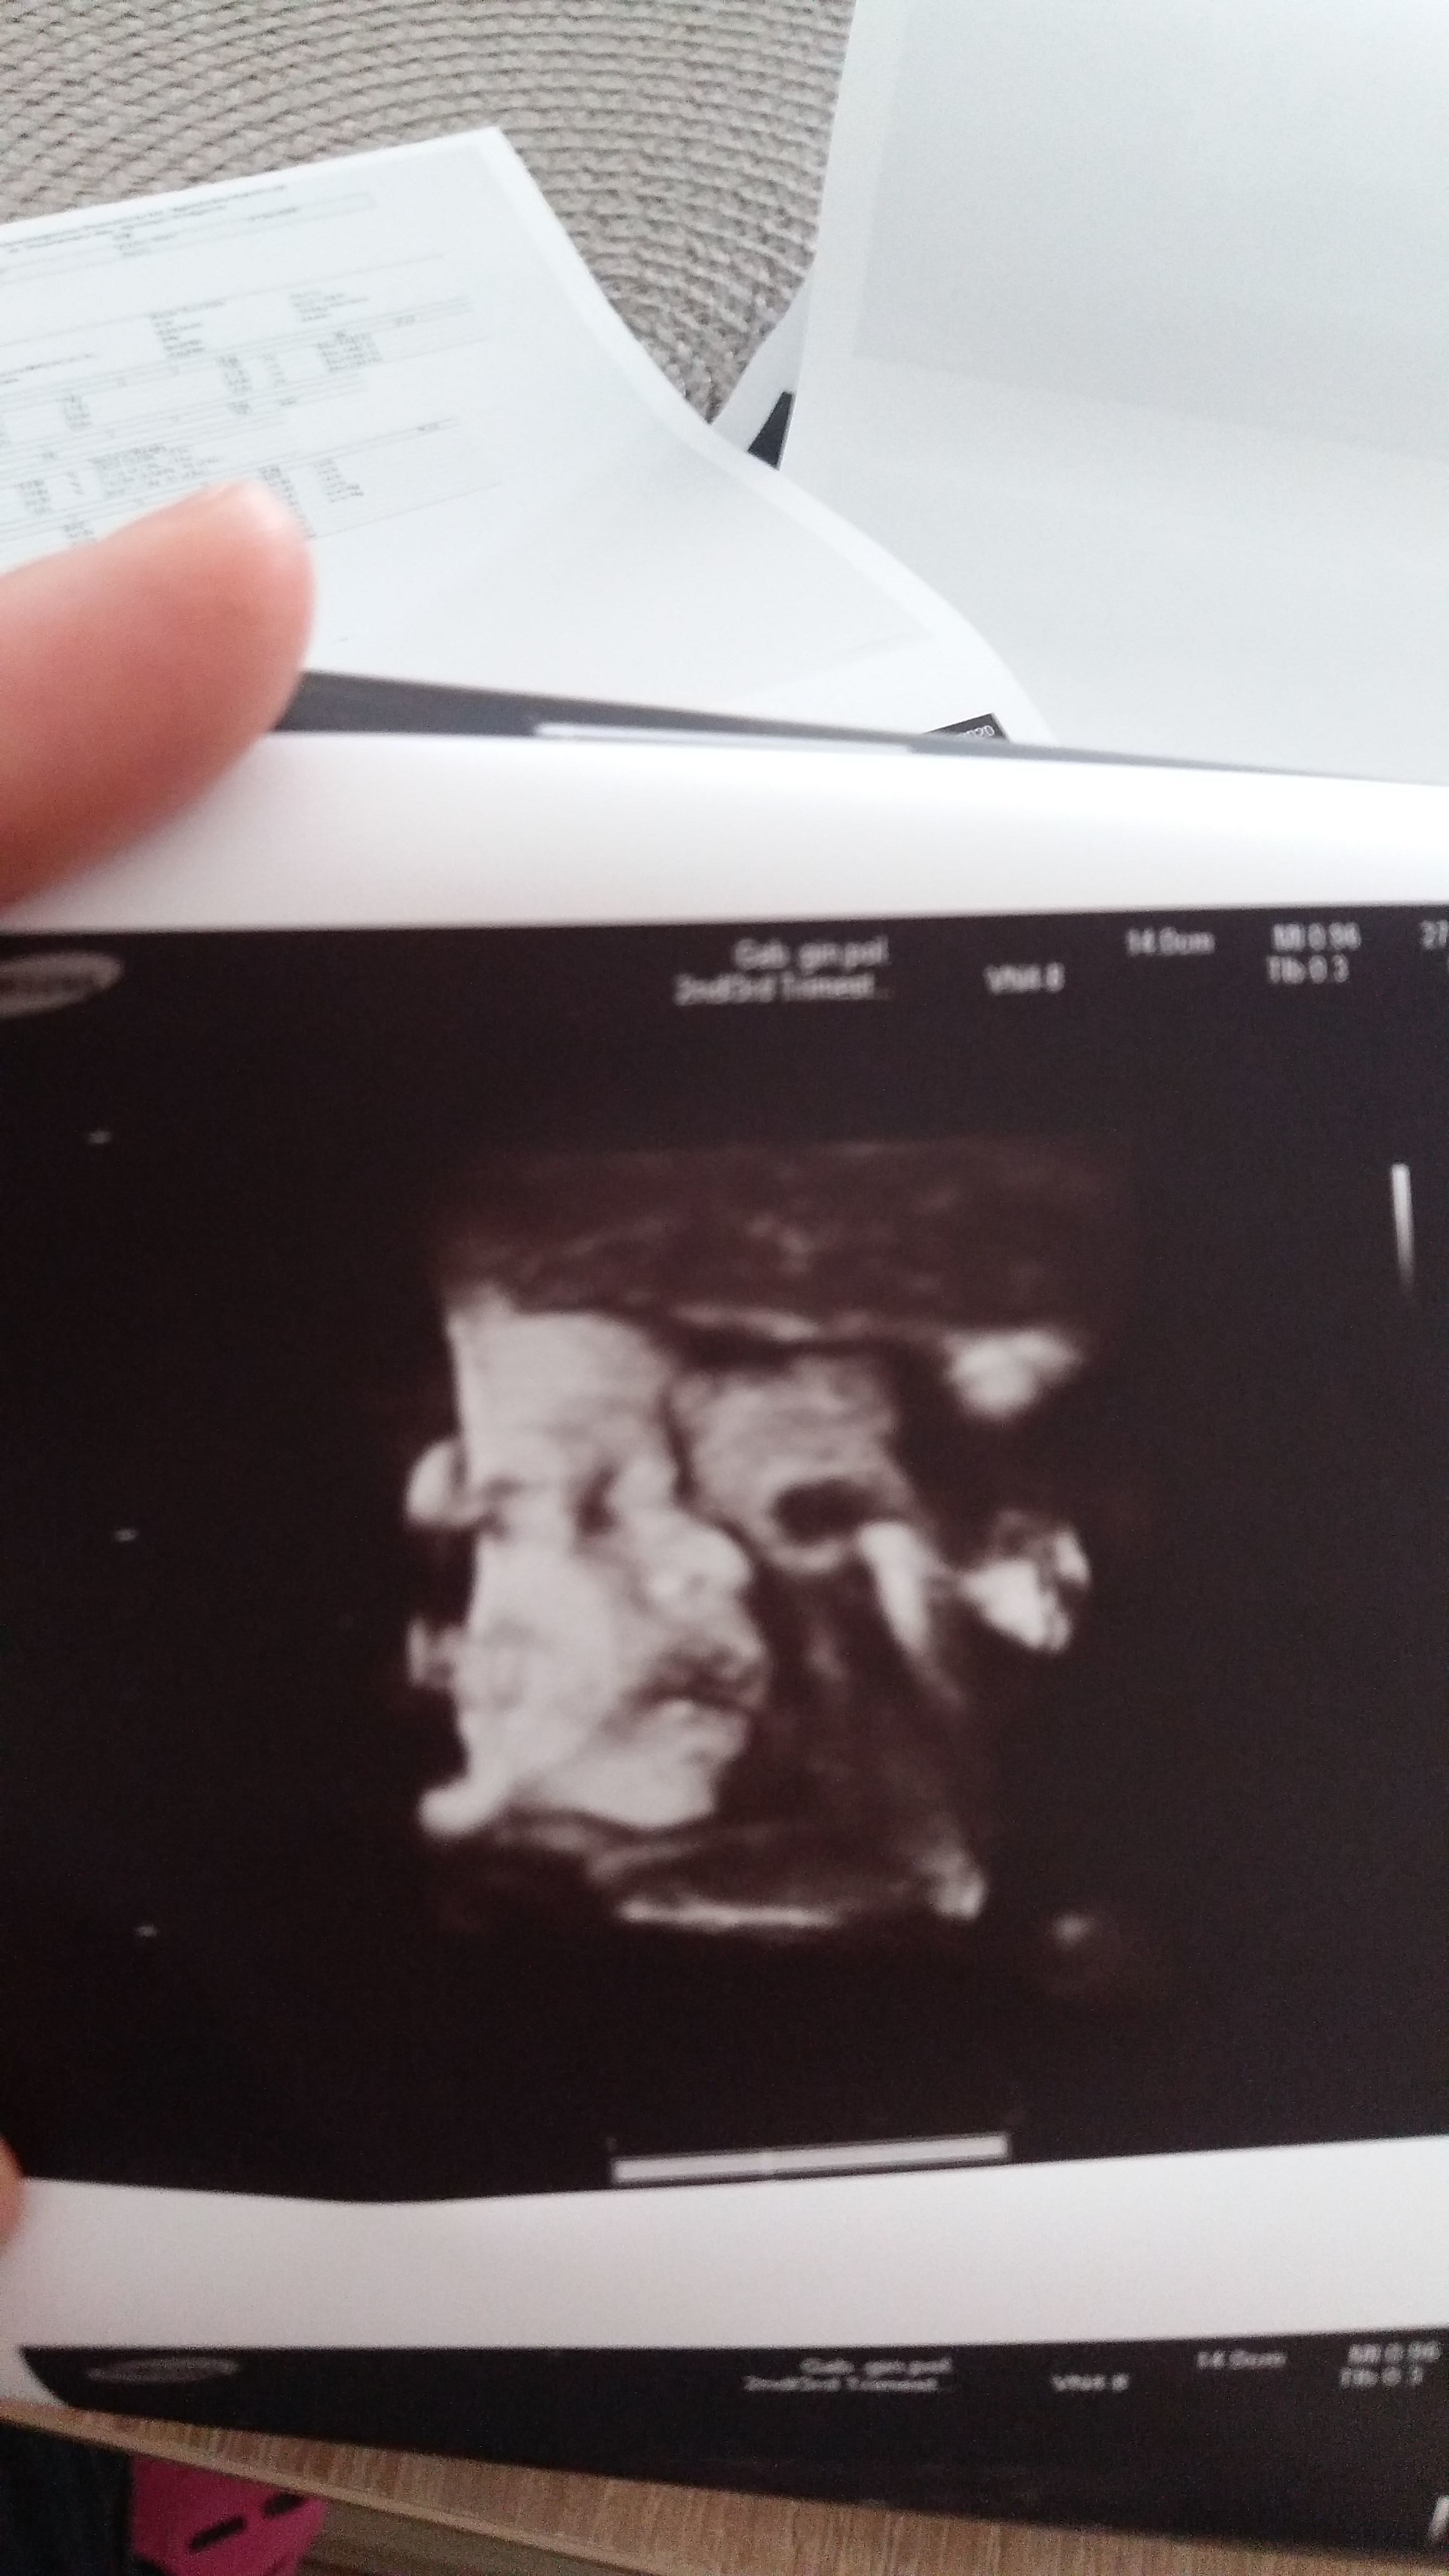

No to super. No widzisz krwiaki pojawiają się bardzo czesto najważniejsze zeby nie powodował odklejania kosmówki. Uważaj na siebie i kontroluj wielkość tego paskudztwa a wszystko będzie dobrze. Ja przy krwiakach brałam też nospę 3xdz. Nie życzę ale gdyby się znowu pojawiło krwawienie to się nie stresuj . Jak jest krwiak to może się to jeszcze zdarzyc. Zdrówka. Ja dzis po prenatalnym III trymestru i u mnie wszystko super dzidzia zdrowa krwiaki mimo wielości pięści nic mojemu" knedelkowi" nie zrobiły

• IMG-20200427-WA0007.jpeg